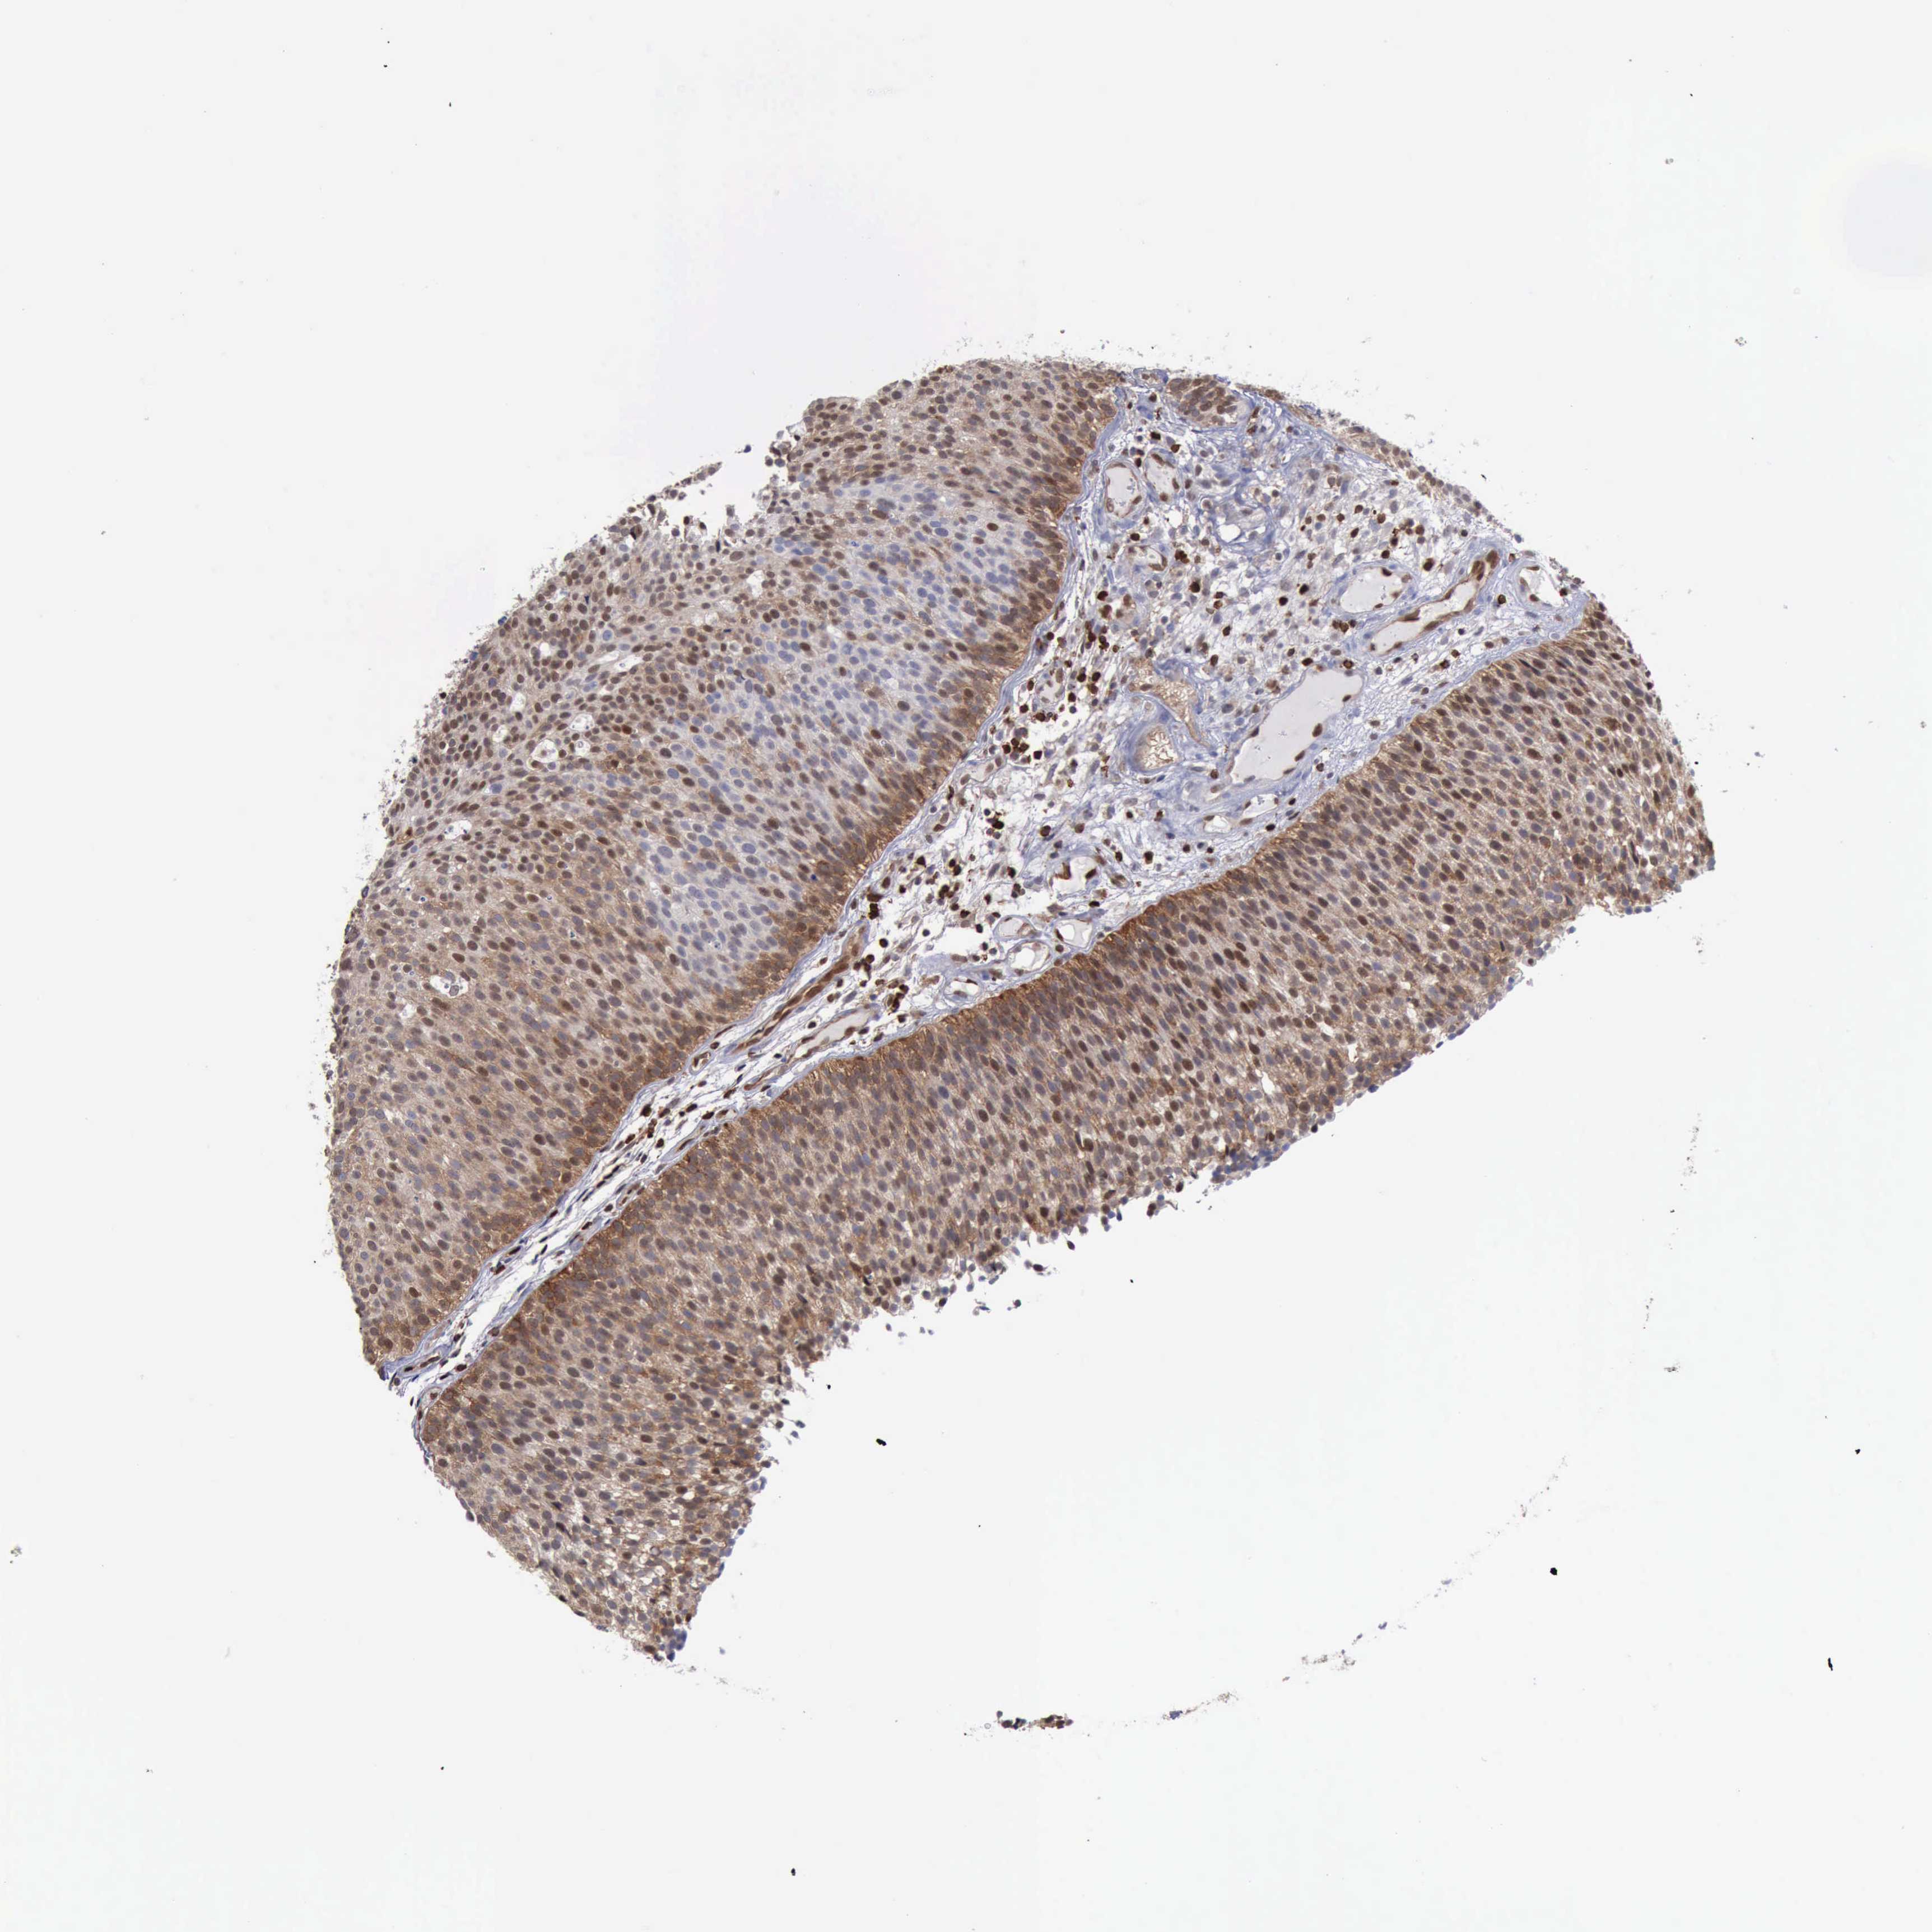

UROTHELIAL CANCER - Protein expressioni

A mouse-over function shows sample information and annotation data. Click on an image to view it in a full screen mode. Samples can be filtered based on level of antibody staining by selecting one or several of the following categories: high, medium, low and not detected. The assay and annotation is described here.

Note that samples used for immunohistochemistry by the Human Protein Atlas do not correspond to samples in the TCGA dataset.

Antibody stainingi

Antibody staining in the annotated cell types in the current human tissue is reported as not detected, low, medium, or high, based on conventional immunohistochemistry profiling in selected tissues. This score is based on the combination of the staining intensity and fraction of stained cells.

Each image is clickable and will lead to virtual microscopy that enables deeper exploration of all samples and also displays staining intensity scores, fraction scores and subcellular localization as well as patient and tissue information for each sample.

Antibody HPA001032

Antibody HPA027214

Antibody CAB037024

Staining

High

Medium

Low

Not detected

Intensity

Strong

Moderate

Weak

Negative

Quantity

>75%

75%-25%

<25%

None

Location

Nuclear

Cytoplasmic/membranous

Cytoplasmic/membranous,nuclear

Urothelial carcinoma, High grade

Urothelial carcinoma, Low grade

Urothelial carcinoma, NOS